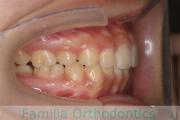

No.20V-496

- 叢生

- 年齢:

- 15歳

- 性別:

- 女性

- 抜歯部位

- 上:

- 84|58

- 下:

- 8558

全体的なでこぼこを治したいということで来院されました。上顎は右は4,左と下顎両側は5番を抜歯して、マルチブラケット法にて治療を行いました。2年強、25回程度の通院をしていただきました。

非常に強いでこぼこですので、後戻りのリスクは高めであると思われます。